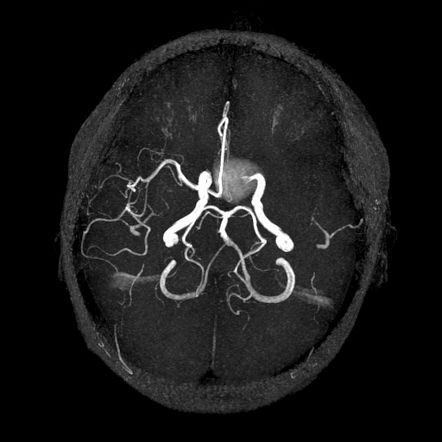

About 85% of cases of subarachnoid hemorrhage are attributed to ruptured berry aneurysm. The aneurysm is most commonly present at anterior communicating artery, posterior communicating artery, and middle cerebral artery. Reference: Davidson's Principles and Practice of Medicine Image via: https://radiopaedia.org/images/36684192?case_id=58816